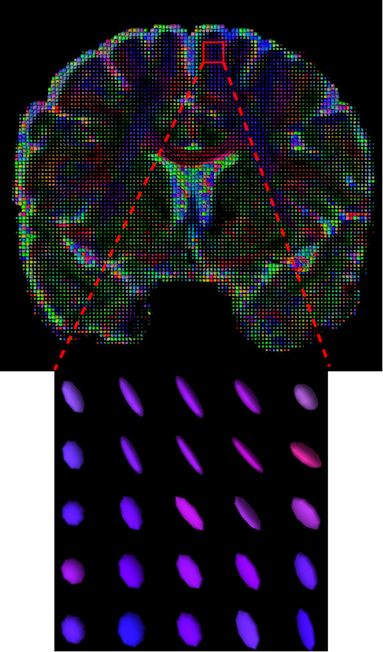

The visualization of inpainted results (showing the whole diffusion tensor for each voxel) generated from different models are demonstrated in Figure 3, where the tensor is represented in RGB coding that colours red, green and blue represent diffusion in the x, y, and z axes respectively. One typical example of reconstruction in the disrupted ROIs has been zoomed for visualization. Compared to the ground truth, TW-BAG is able to generate more distinct orientations following the original distribution and intensity across sagittal, coronal and axial views, which could demonstrate water diffusivity (denoted by eigenvalues of tensor model) more accurately. As indicated in Figure 4, the boundaries and textures of the FA map for TW-BAG are less blurry than the other competing models, validating the effectiveness of TW-BAG from a neuroscience perspective.